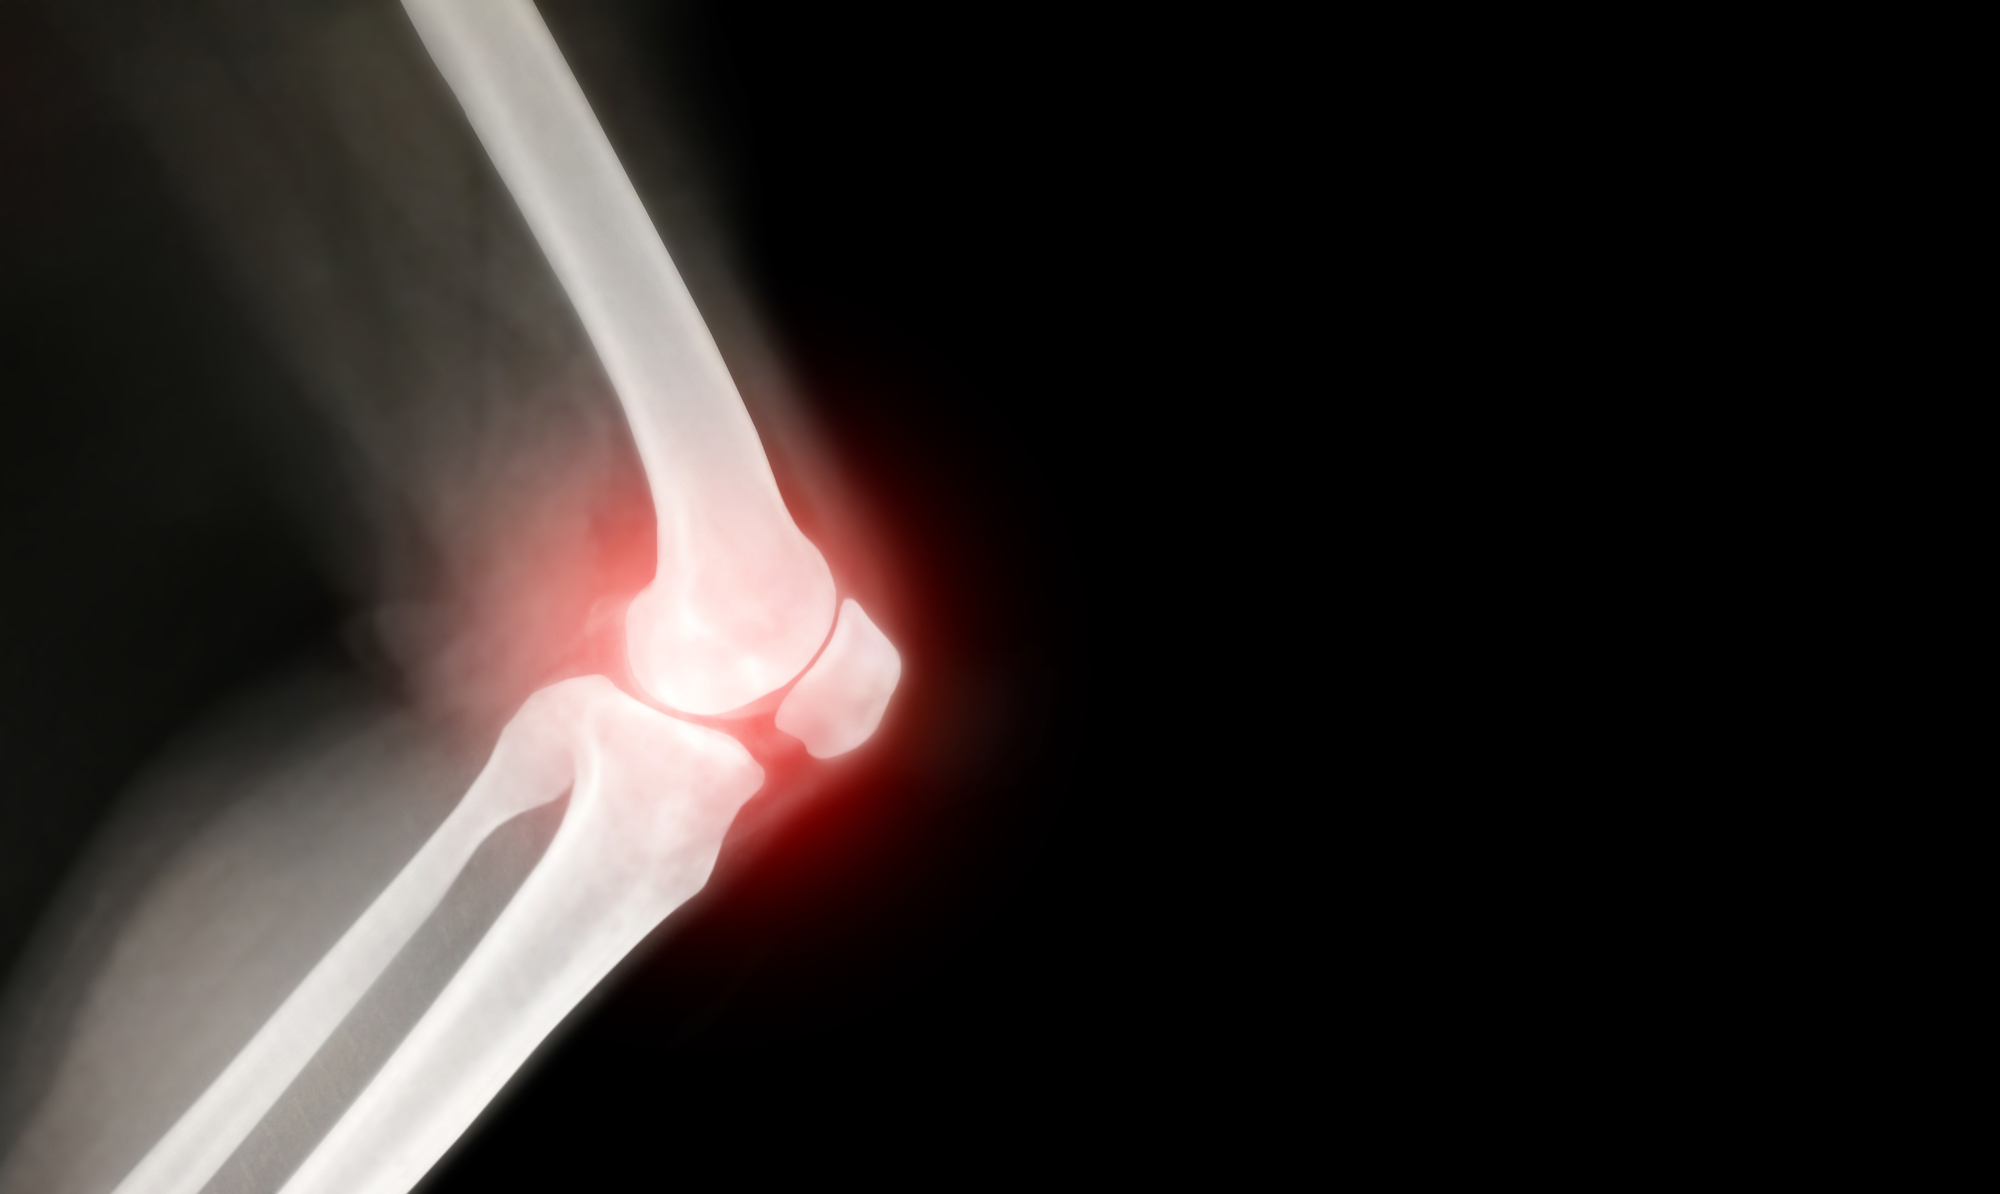

膝の関節の表面を覆っている軟骨が、長年の使用や負担によってすり減り、膝に痛みや腫れ、変形が生じる病気です。

軟骨は骨と骨が直接ぶつかるのを防ぐクッションの役割を果たしていますが、これがすり減ることで骨同士がこすれ合い、強い痛みや炎症を引き起こします。

【X線(レントゲン)検査】

骨の状態を確認します。骨と骨の隙間(軟骨の厚み)が狭くなっていないか、トゲのような骨ができていないかなどを調べます。